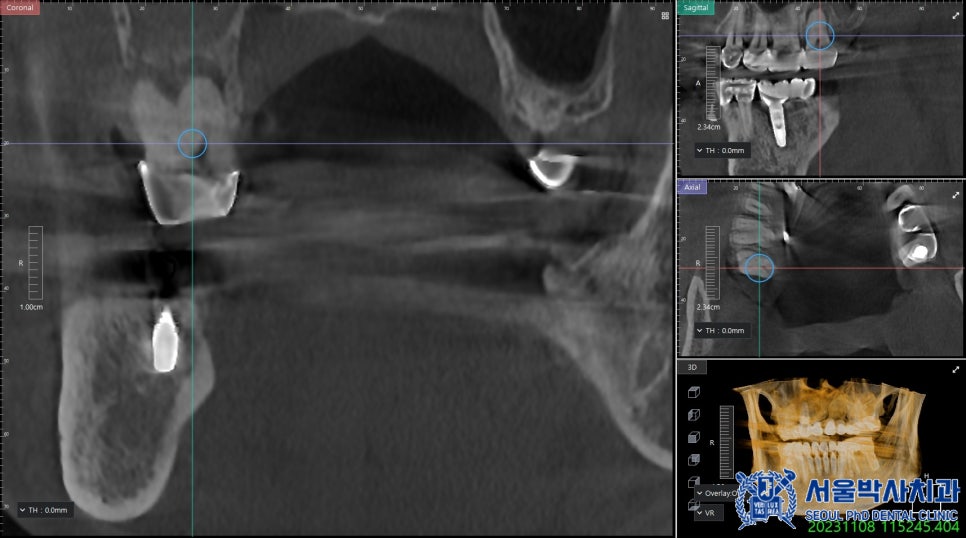

이 과정에서 중요한 것은 임플란트가

정밀한 위치와 각도로 식립되는 것입니다.

임플란트의 식립각도는 수술 성공률과

직결되기 때문에 작은 오차도 결과에

큰 영향을 미칠 수 있습니다.

신흥동치과 서울박사에서는 이를 보완하기 위해

네비게이션 시스템을 활용하여

컴퓨터 시뮬레이션을 통해 미리 식립 위치를

정밀하게 계산하고 수술 가이드를 제작하여

정밀한 위치에 임플란트를 식립합니다.